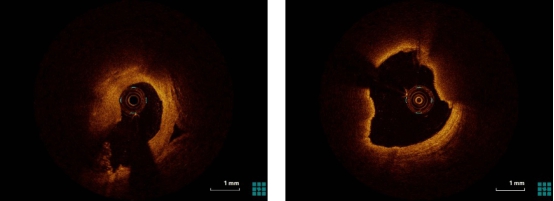

左冠静脉桥血管药物球囊治疗前后OCT影像对比

右冠静脉桥血管药物球囊治疗前后OCT影像对比

团队凭借对上万例OCT影像的精准分析经验,对该患者的术中影像进行了充分的评估、判断。OCT结果提示,两处再狭窄桥血管粥样硬化斑块均为局限病变,长度10mm以内,斑块内脂质成分虽多,但从象限分布情况及体积来看,充分的球囊扩张预期不会引起无复流等并发症,所以该患者在OCT精准的指导下综合评估不需要进行支架植入,药物球囊的精确使用是对患者最佳的诊疗方式。